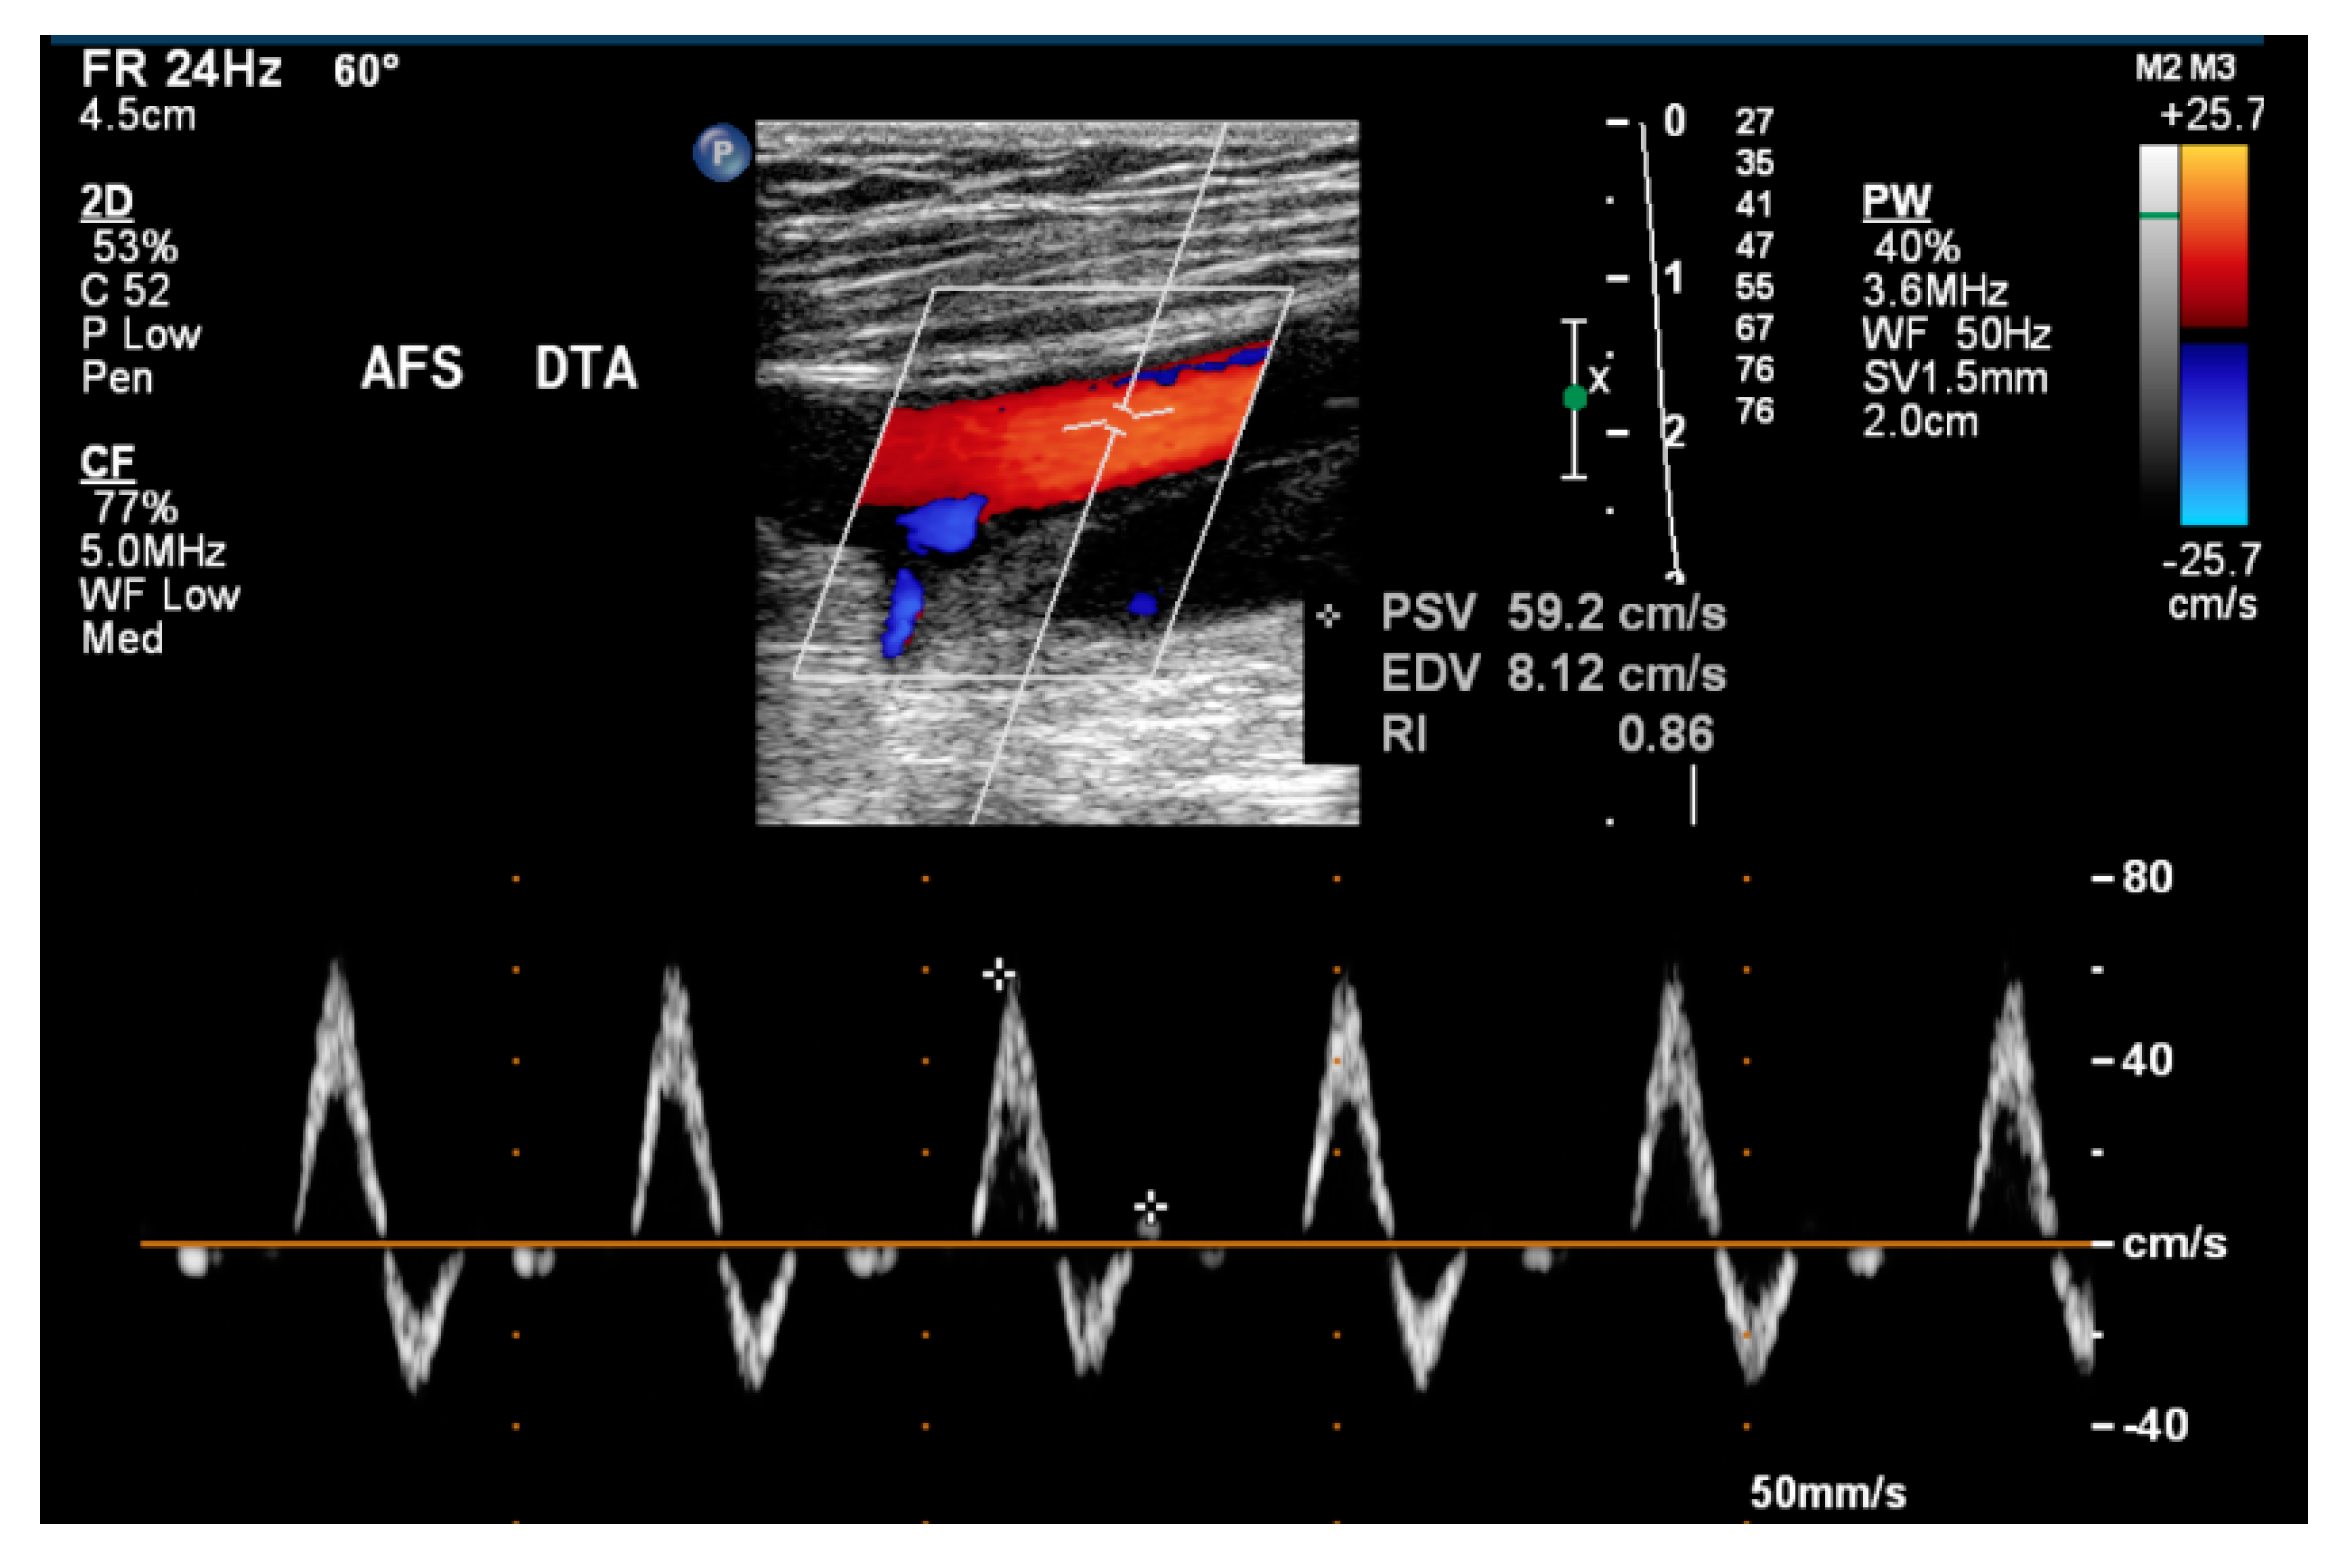

2.2. Instruments

2.3. Procedures